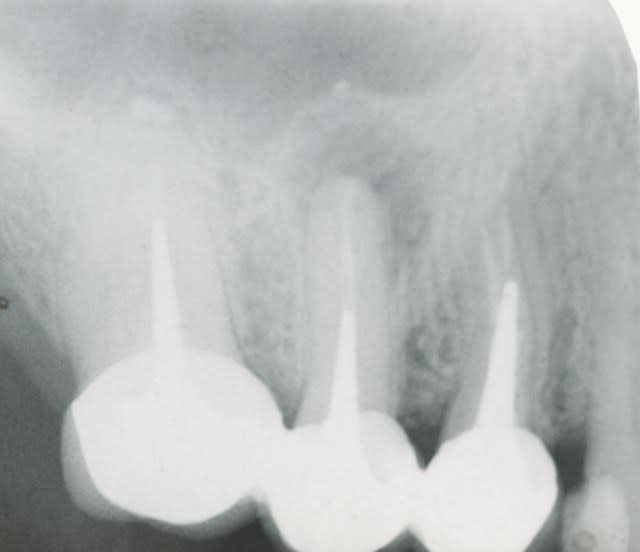

comme promis resto-radio

ci joint 2 radios de controle a 10 ans .

pas de resorption au tiers apical pas d ankylose .